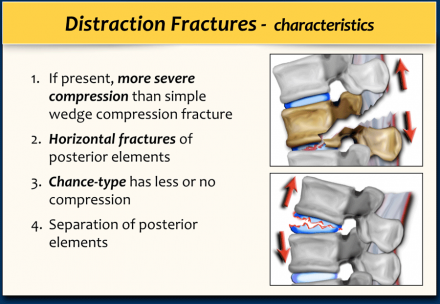

Distraction

A distraction injury is separation or pulling apart of two adjacent vertebrae.

It is a severe injury since there is a high chance of cord injury when

its osseous and ligamentous supporting structures are pulled apart.

A distraction injury on the posterior side can lead to a compression fracture on the anterior side.

So be sure not to underestimate the injury by only looking at the compression fracture and overlooking the distraction injury.

In some cases it is difficult to decide whether you are dealing with distraction combined with a compression fracture or with a compression fracture with PLC-injury.

If the distraction is the main feature, then the morphology is distraction, i.e. 4 points.

In these cases the PLC is always involved, resulting in a total of 7 points for the TLICS-score.

If compression is the main feature, then the morphology is burst, i.e. 2

points combined with the PLC injury making a total of 5 points.

In both cases the patient is a surgical candidate.

In this case the main findings are the horizontal fractures of the posterior elements.

The vertebral body fractures show hardly any compression.

Notice that there are 3 vertebrae involved.

Only the level with the highest score counts.

TLICS score based on imaging is 7 points:

- Distraction: 4 points

- PLC involvement: 3 points

In this case there is severe compression of the vertebral body.

However the most important findings are the horizontal fractures of the posterior elements.

TLICS score based on imaging is 7 points.